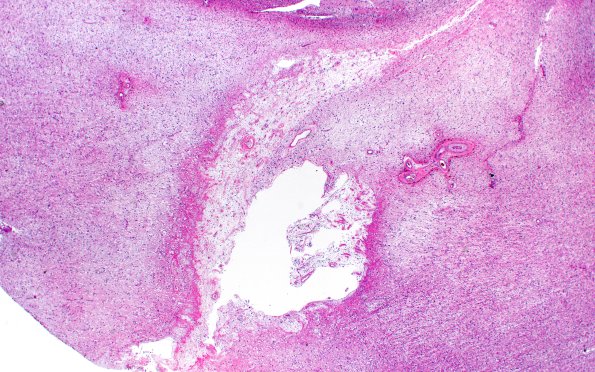

20A1 Arteriolosclerosis (Case 20) N1 H&E 2X

No history available. Note the small infarct and the associated arteriolosclerotic vasculature. (H&E)